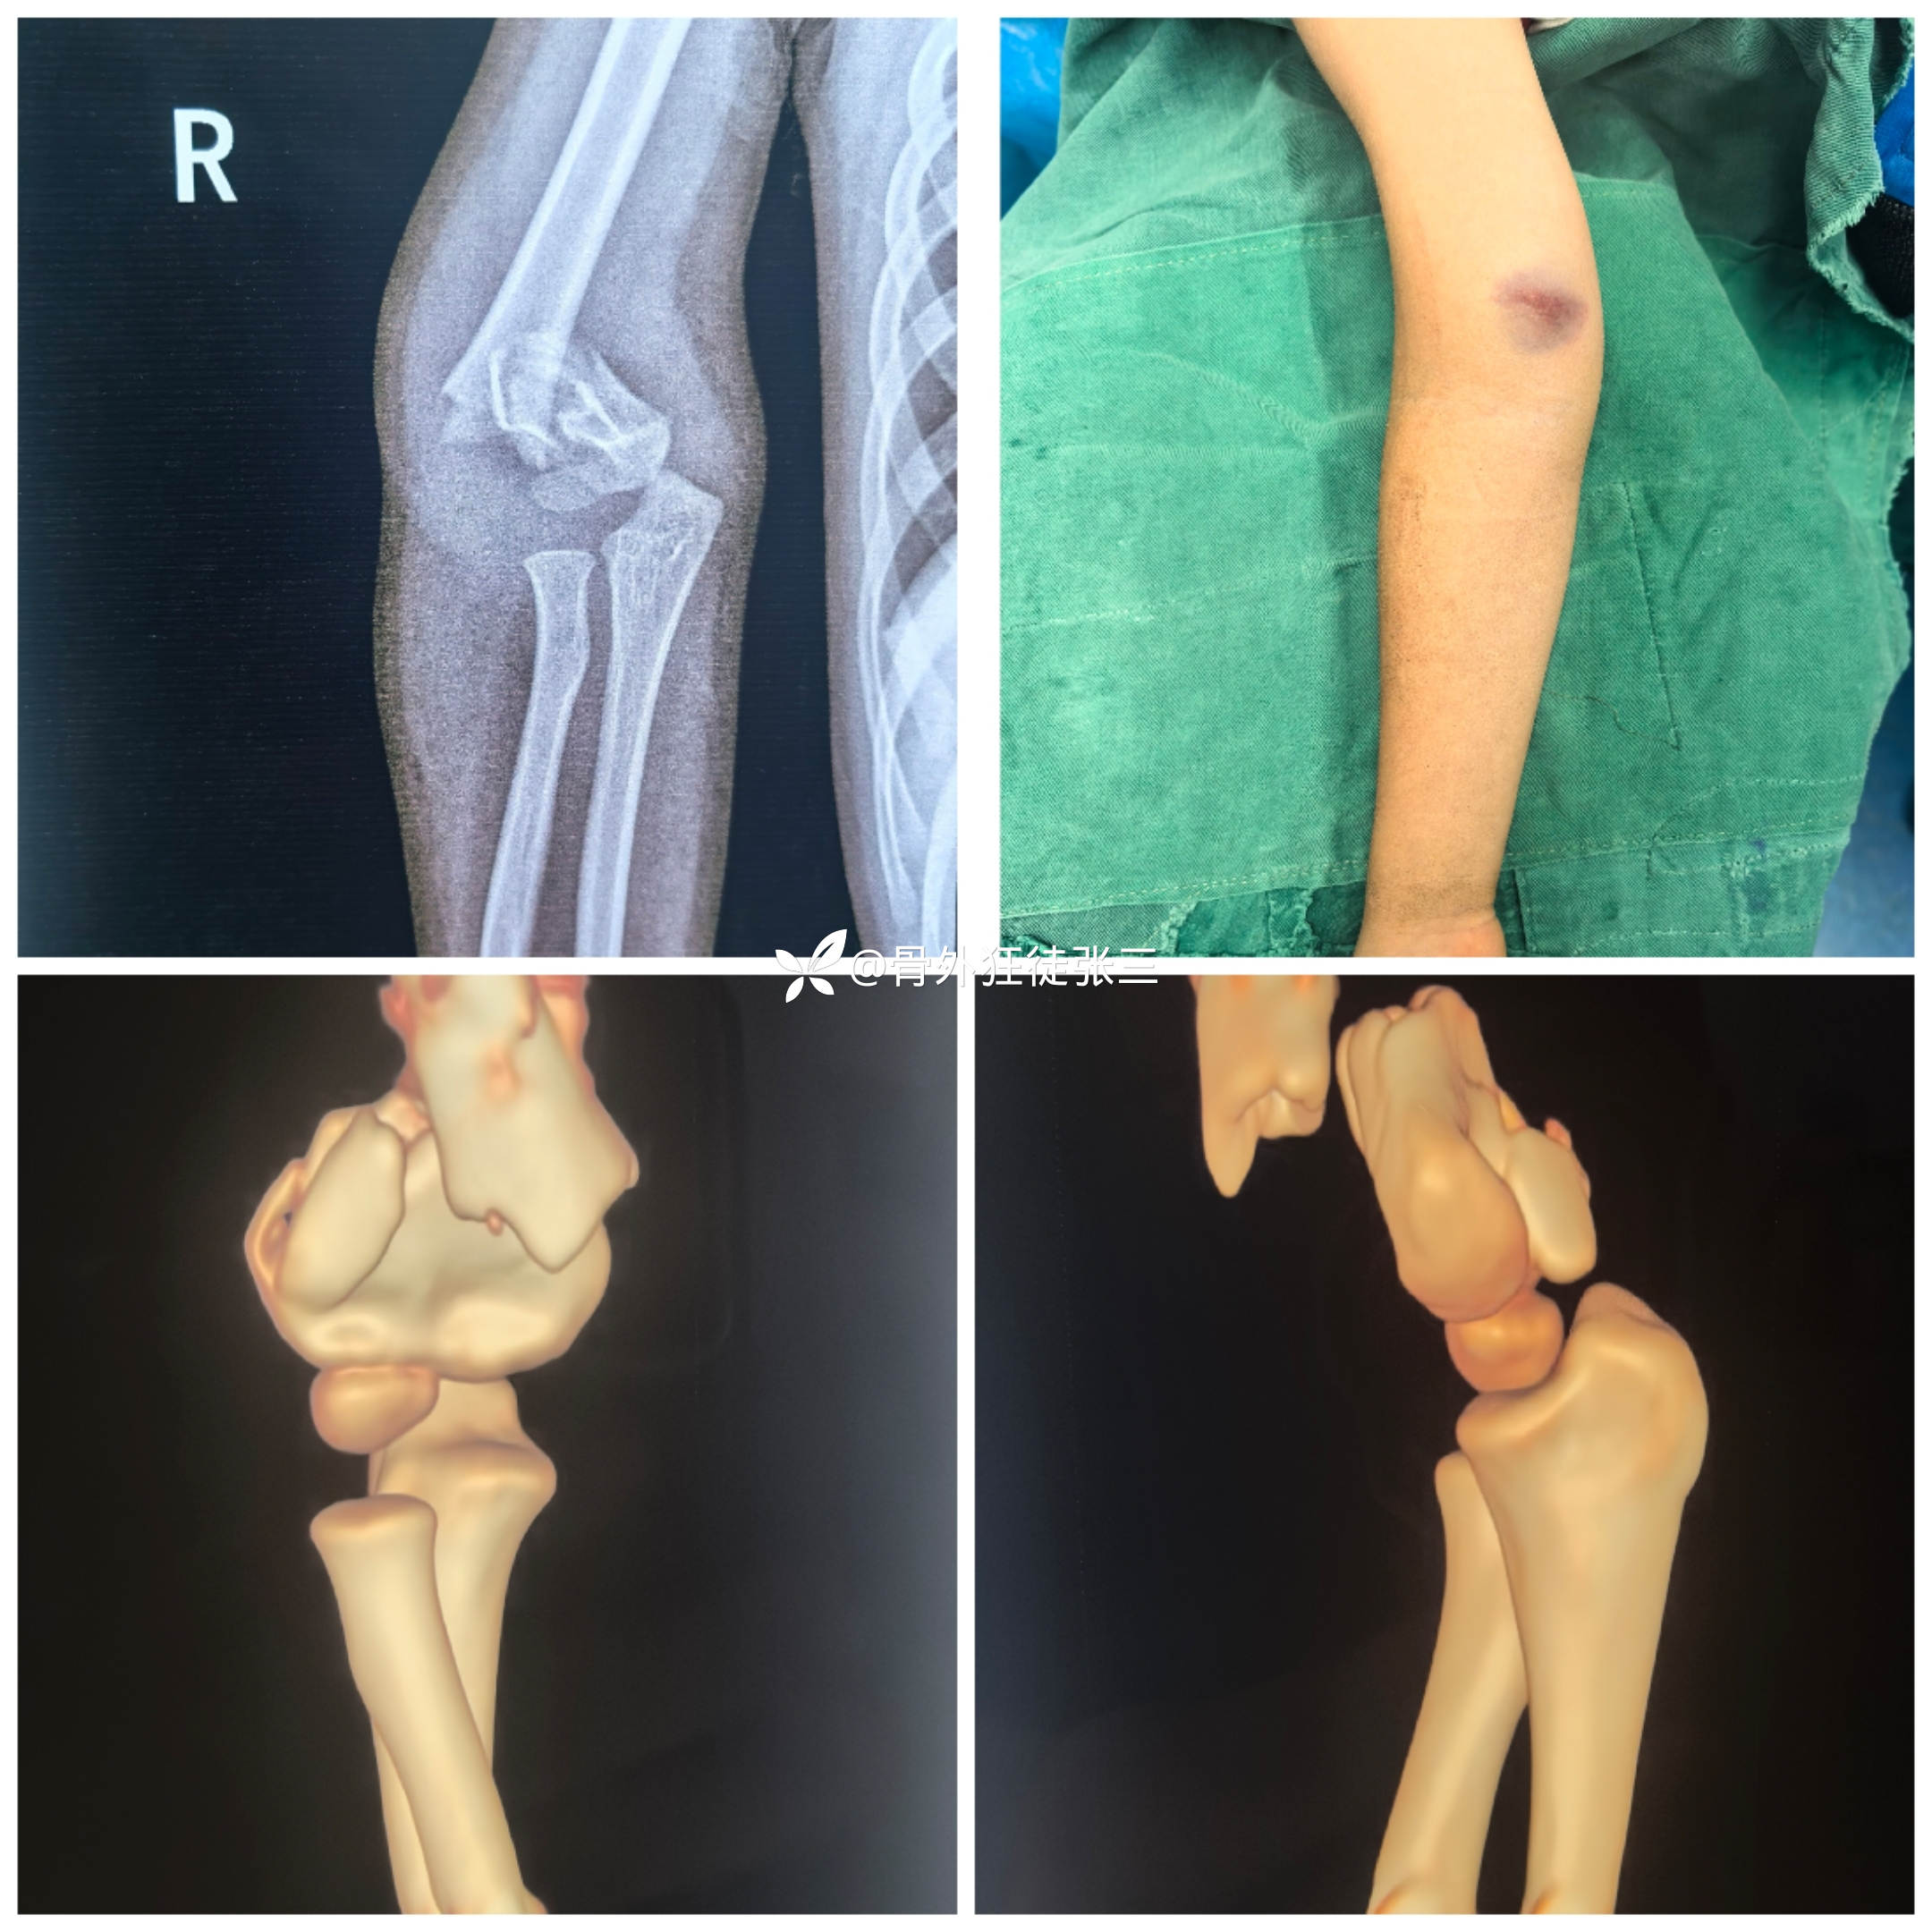

病例一:

5岁,男,高位髁上(粉碎性骨折)

术前影像: